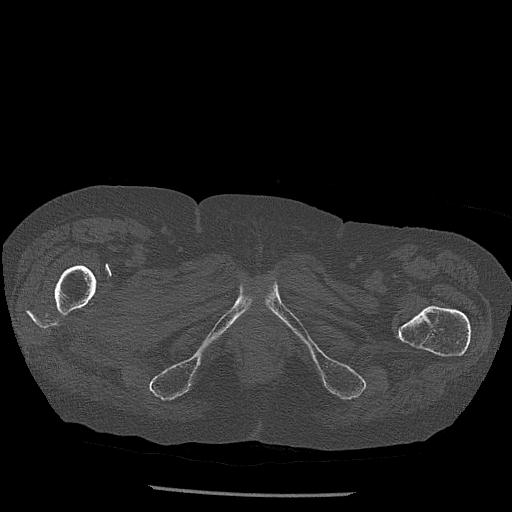

100703 1/27 両股正面+軸 1/29 両股正面+軸 94歳女性 パンソンロン